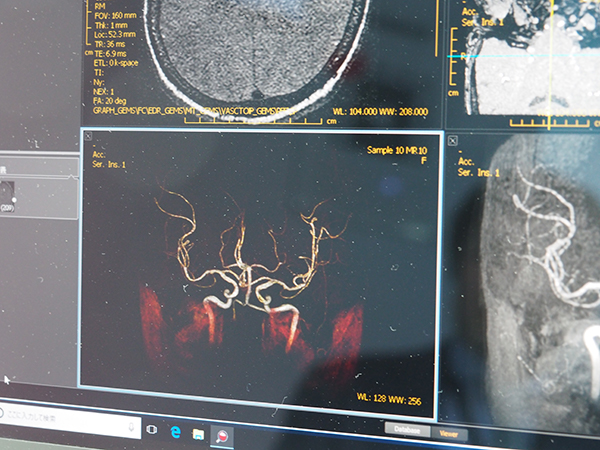

ONIS 3は,異なるベンダーのPACSを相互に接続可能にするPACSブリッジ機能を特長として,「ONIS3サイトサーバ」「ONIS3ビューワ」「ONIS3リモート」「ONIS Webサーバ」などの製品群(スイート)で構成される。ONIS 3のサーバとビューワを組み合わせれば,シリーズの全データをダウンロードする前に指定の画像を取得できる“スマートダウンロード機能”や,DICOMの動画像規格に準拠したMPEG4/H.264の“ストリーミング再生機能”を利用できる。ONIS 3では,動画像データについて従来のマルチフレームのDICOM動画像ではなく,MPEG4圧縮されたDICOM規約準拠のフォーマットが扱えることが特長で,手術野の記録映像など長時間の動画像をDICOMサーバで一括して管理できる。動画像データはサーバやネットワークなどのインフラも含めて別システムで管理されることが多いが,改正個人情報保護法の施行によって,医療情報のより厳格な管理が求められる中で,動画像データをDICOM規格としてカプセル化し改ざん不可の形式で管理できるONIS 3のメリットをアピールした。

ONIS3ビューワではMIP,MPR,VRの作成,表示にも対応